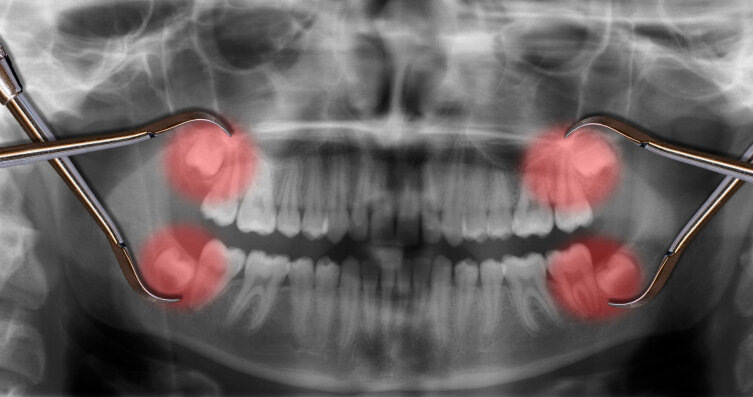

Зубы мудрости обычно растут в этих местах